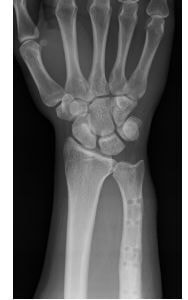

遠位橈尺関節の不安定性を伴う尺骨突き上げ症候群に対する尺骨短縮術の術前(左)と術後(右)。術後には関節の不安定性が消失し、疼痛も出現しなくなった。

前腕にある2本の骨:橈骨(とうこつ)と尺骨(しゃっこつ)の長さが有意に異なることによって起こる障害の一つです。尺骨突き上げ症候群は、尺骨が橈骨よりも長いことによって起こる手関節尺側部の障害の総称です。尺骨が橈骨より長いこと自体は悪いことではありませんが、長年の使用により疼痛を生じる原因となる場合があります。尺骨が長くなる原因のほとんどは先天的な素因によるものですが、橈骨の骨折によって生じることもあります。

症状は、手の使用に伴う手関節尺側部の疼痛ですが、疼痛の原因は、尺骨の突き上げによる三角線維軟骨(関節円板)の損傷、手根骨の挫傷、橈尺靱帯の損傷のほか、橈尺関節の不適合による関節症変化など様々であり、これが”症候群”と呼ばれる所以です。

治療は、症状の原因に対してピンポイントに行うことが原則ですが、尺骨突き上げ症候群においては『どの要素が最も症状に関与しているか?』を見極めることが困難であるため、相当期間の安静を保っても症状が改善しない場合には、すべての要素を同時に治療すべく『尺骨短縮(骨切り)術』を行います。

具体的には、前腕尺側の皮膚切開から尺骨を骨切して短縮し、プレートとスクリューを用いて固定します。しっかりと固定されれば早期から簡単な手の使用は可能ですが、手関節に負荷が掛かる動作・業務・スポーツは、3ヶ月ほど控えていただく必要があります。